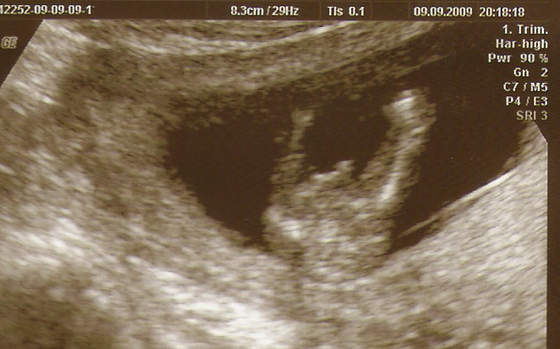

:-)No to przedstawiam Wam mojego Maluszka -

Zobacz załącznik 165063

Z prawej strony noga, z lewej strony noga (mniejsza bo nia machnal) a miedzy nimi COS :-)

Zobacz załącznik 165064